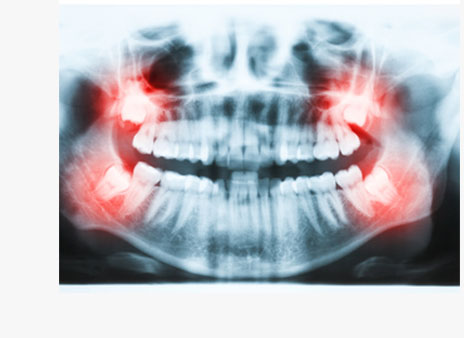

不能正常长出、或牙位阻生、埋伏,及其他对牙齿造成不良影响、反复发炎疼痛、已经龋坏的智齿。

| 传统二维X光片容易造成视野不清晰,无法准确判断牙根 | 影像设备 | 口腔CT全方位了解牙根部及神经情况 |